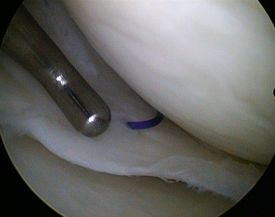

Gelenkspiegelung (Arthroskopie)

HD-Bilder aus dem Schulter- und Kniegelenk

In der Unfallchirurgie der Klinik Bogen kommen neben den herkömmlichen offenen Operationsverfahren insbesondere auch minimal invasive OP-Techniken zum Einsatz. Die sogenannte Schlüsselloch-Chirurgie heißt im Gelenkbereich Arthroskopie oder Gelenkspiegelung.

- zielgenaue Behandlung (gute Sicht dank stark vergrößerter Gelenkdarstellung über HD-Monitor)

Kniegelenk

- Glättung der Knorpeloberfläche

- Spülung des Gelenks

- Microfracturing: Über feine Anbohrungen des Knochens tritt Knochenmark mit Blut- und Stammzellen aus, die eine knorpelähnliche Struktur und Oberfläche auf dem Knorpeldefekt herstellen können.

- Knorpelzelltransplantation